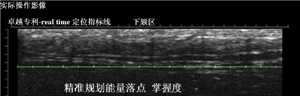

Ulthera極限音波拉皮獨(dú)創(chuàng)“定位指標(biāo)線”專利,針對(duì)皮膚筋膜分層拉提,能精準(zhǔn)掌握能量落點(diǎn),細(xì)膩準(zhǔn)確,安全無虞零誤差。

如何區(qū)分真假超聲刀美容儀器(圖)_28

(Ulthera極線音波拉皮獨(dú)創(chuàng)“定位指標(biāo)線”專利)

而山寨版的超聲刀沒有這一DeepSee界面,因此醫(yī)師不能直觀看到超聲聚焦能量的改善層次是否在SMAS層,因此效果大打折扣。此外,山寨版超聲刀的能量改善層次呈曲線狀,主要是擔(dān)心其形成的熱凝結(jié)點(diǎn)不能精準(zhǔn)作用于SMAS層上,因此作用層次采用波浪線條狀,用“瞎貓碰上死耗子”的概率來碰運(yùn)氣。就存在部分能量可能作用于SMAS層上,部分能量僅作用于真皮層上。